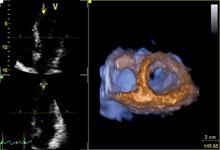

Hardware and software advances are enabling echocardiography to greatly expand its capability with increased quantification accuracy, ease-of-use, increased workflow efficiencies and wider use outside of echo labs. Today, cardiovascular ultrasound systems are being integrated into point-of-care for triage, and in operating rooms and cath labs for procedural guidance to cut the use of contrast and ionizing radiation.